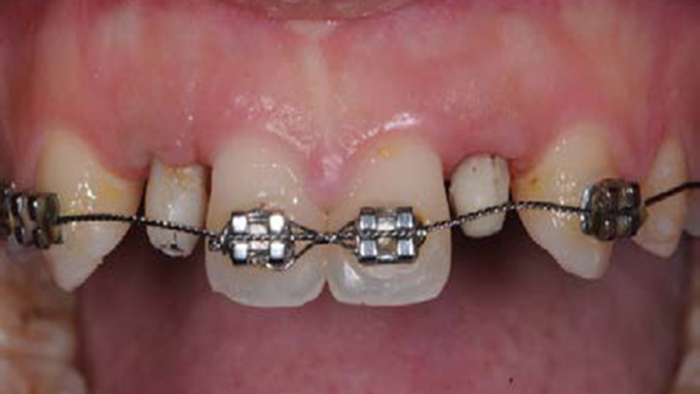

Clinical case: Patient-centered approach: treatment strategy for Root Membrane Technique & delayed implant placement

- Courtesy of Dr. Yoshiharu Hayashi, Japan -

Socket Shield Technique, anterior esthetics, maxillary anterior, esthetic, esthetics, delayed implant placement, socket preservation, AnyRidge, Root Membrane Kit, Root Membrane Technique, Partial Extraction Therapy, PET, esthetic zone, fuse abutment, Dr. Yoshiharu Hayashi,#11,#21,#22

Products:

AnyRidge implant system, fuse abutment Root membrane kit, PET Kit